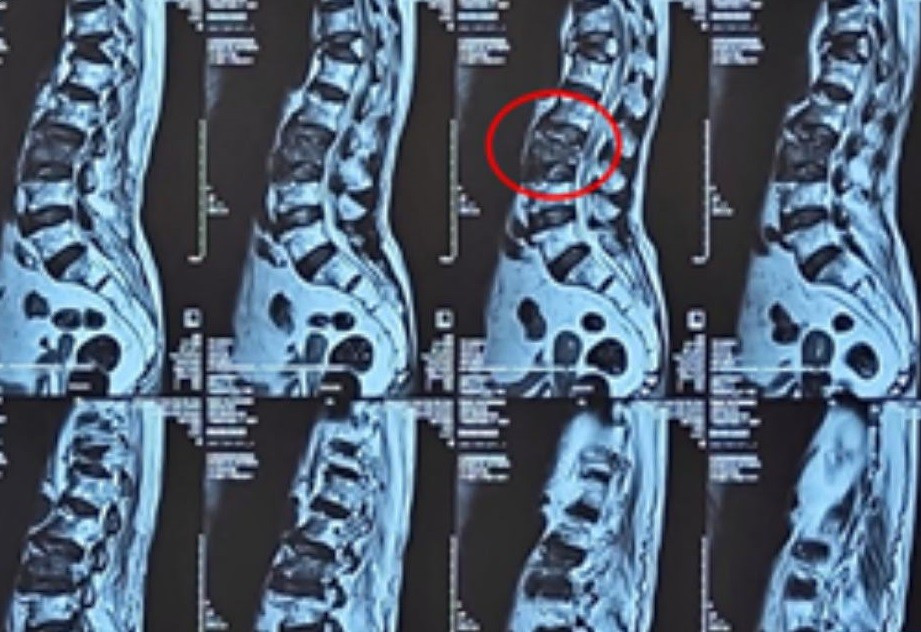

Kết quả chụp MRI cột sống cho thấy cụ bà bị gãy xẹp cấp tính thân đốt sống thắt lưng L3, kèm phù tủy xương. Đây chính là nguyên nhân trực tiếp gây ra cơn đau dữ dội kéo dài. Trường hợp trở nên phức tạp hơn khi người bệnh có tuổi đời rất cao, kèm nhiều bệnh lý nội khoa và nghi ngờ tổn thương u phổi được phát hiện trong quá trình chuẩn bị tiền phẫu.